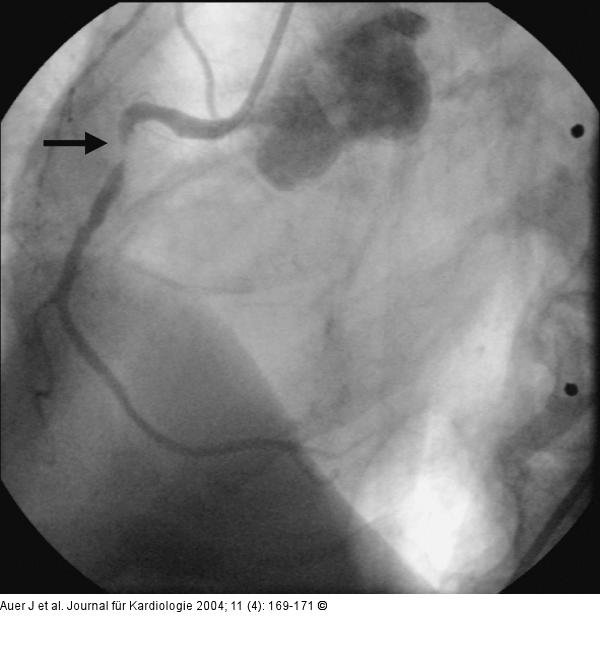

Abbildung 8: Akutes Koronarsyndrom - Stenose der linken Herzkranzarterie Progression in der proximalen rechten Herzkranzarterie mit einer nunmehr höchstgradigen Stenose |

Progression in der proximalen rechten Herzkranzarterie mit einer nunmehr höchstgradigen Stenose |